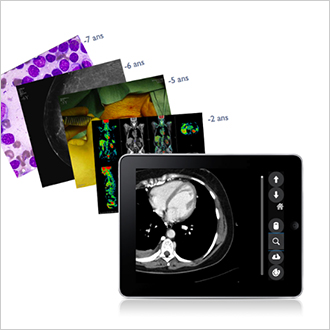

TM-Community

The TM-Community is a cloud-based solution allowing hospital sites to exchange medical files with each other. These exchanges include all types of documents (PDF, DICOM, JPEG, etc.) and are secured and traced. This solution makes it possible, among other things, to request second diagnostic opinions, to send a file to a centre of expertise or to send images on a daily basis to a referring centre.